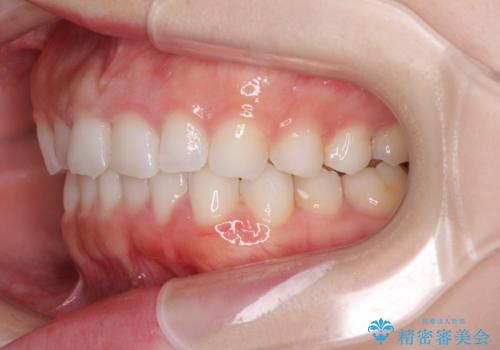

デコボコと深い咬み合わせの改善 インビザラインによる矯正治療

- 口元のデコボコと深い咬み合わせ(ディープバイト)を気にして来院された患者様です。

インビザラインによる上下歯列の拡大と、IPR(歯と歯の間を削る)にるスペースの獲得により、口元のデコボコとディープバイトを改善することとしました。

インビザラインは、装着していない時間がどれだけ短いかが、治療期間を大きく左右します。こちらの患者様は1日22時間以上、毎日欠かさず装着してくださったため、1年強という短期間で満足のいく歯列に整えることができました。